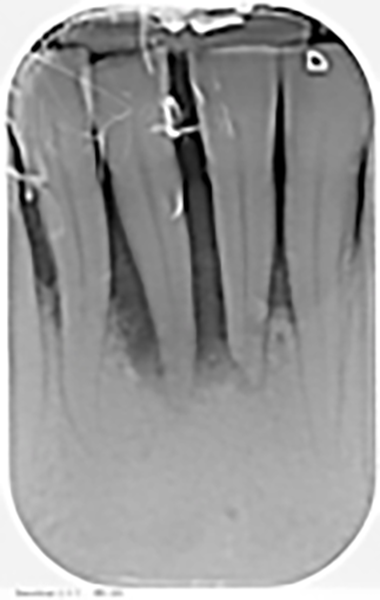

Si presenta alla nostra attenzione una paziente di 40 anni lamentando sensibilità, dolore alla masticazione e mobilità a carico degli incisivi centrali dell’arcata inferiore. Previa anamnesi medica e odontoiatrica si procede con l’esame obiettivo e con gli esami radiografici. Dall’esame obiettivo si osserva come gli elementi 3.1 e 4.1 risultino mobili, dalla radiografia si evidenzia un notevole riassorbimento osseo attorno agli elementi dentari in questione.

Previa anestesia locale si esegue lo scollamento di un lembo a spessore totale per consentire l’avulsione atraumatica degli elementi 3.1 e 4.1 (figure 1a-1b). Si revisionano le cavità alveolari e si posizionano osso bovino deproteinizzato e una membrana di collagene riassorbibile. Si sutura con filo 5/0, si posiziona un maryland bridge per garantire l’estetica in attesa dell’inserimento implantare e si esegue una radiografia di controllo (figure 2-4).

Dalle radiografie (figure 1a, 3 e 11) si nota come ci sia stato un incremento del tessuto osseo.